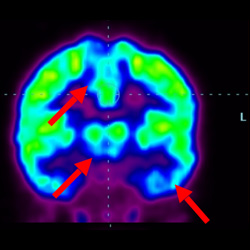

干細(xì)胞治療腦癱后改善的客觀放射學(xué)證據(jù)

細(xì)胞治療后,藍(lán)色和黑色區(qū)域減少,并且看到更活躍的區(qū)域。這表明損傷減少并改善了大腦功能。

細(xì)胞治療前 PET CT 掃描顯示神經(jīng)組織中的藍(lán)/黑色區(qū)域,表明腦癱引起的大腦損傷。

這證明細(xì)胞療法是治療腦癱兒童安全有效的方法。細(xì)胞療法可以更新大腦損傷的核心,并且可以通過 PET CT 掃描來監(jiān)測(cè)大腦的改善情況。這些細(xì)胞療法與標(biāo)準(zhǔn)治療一起促進(jìn)腦癱兒童的生長(zhǎng)和改善。